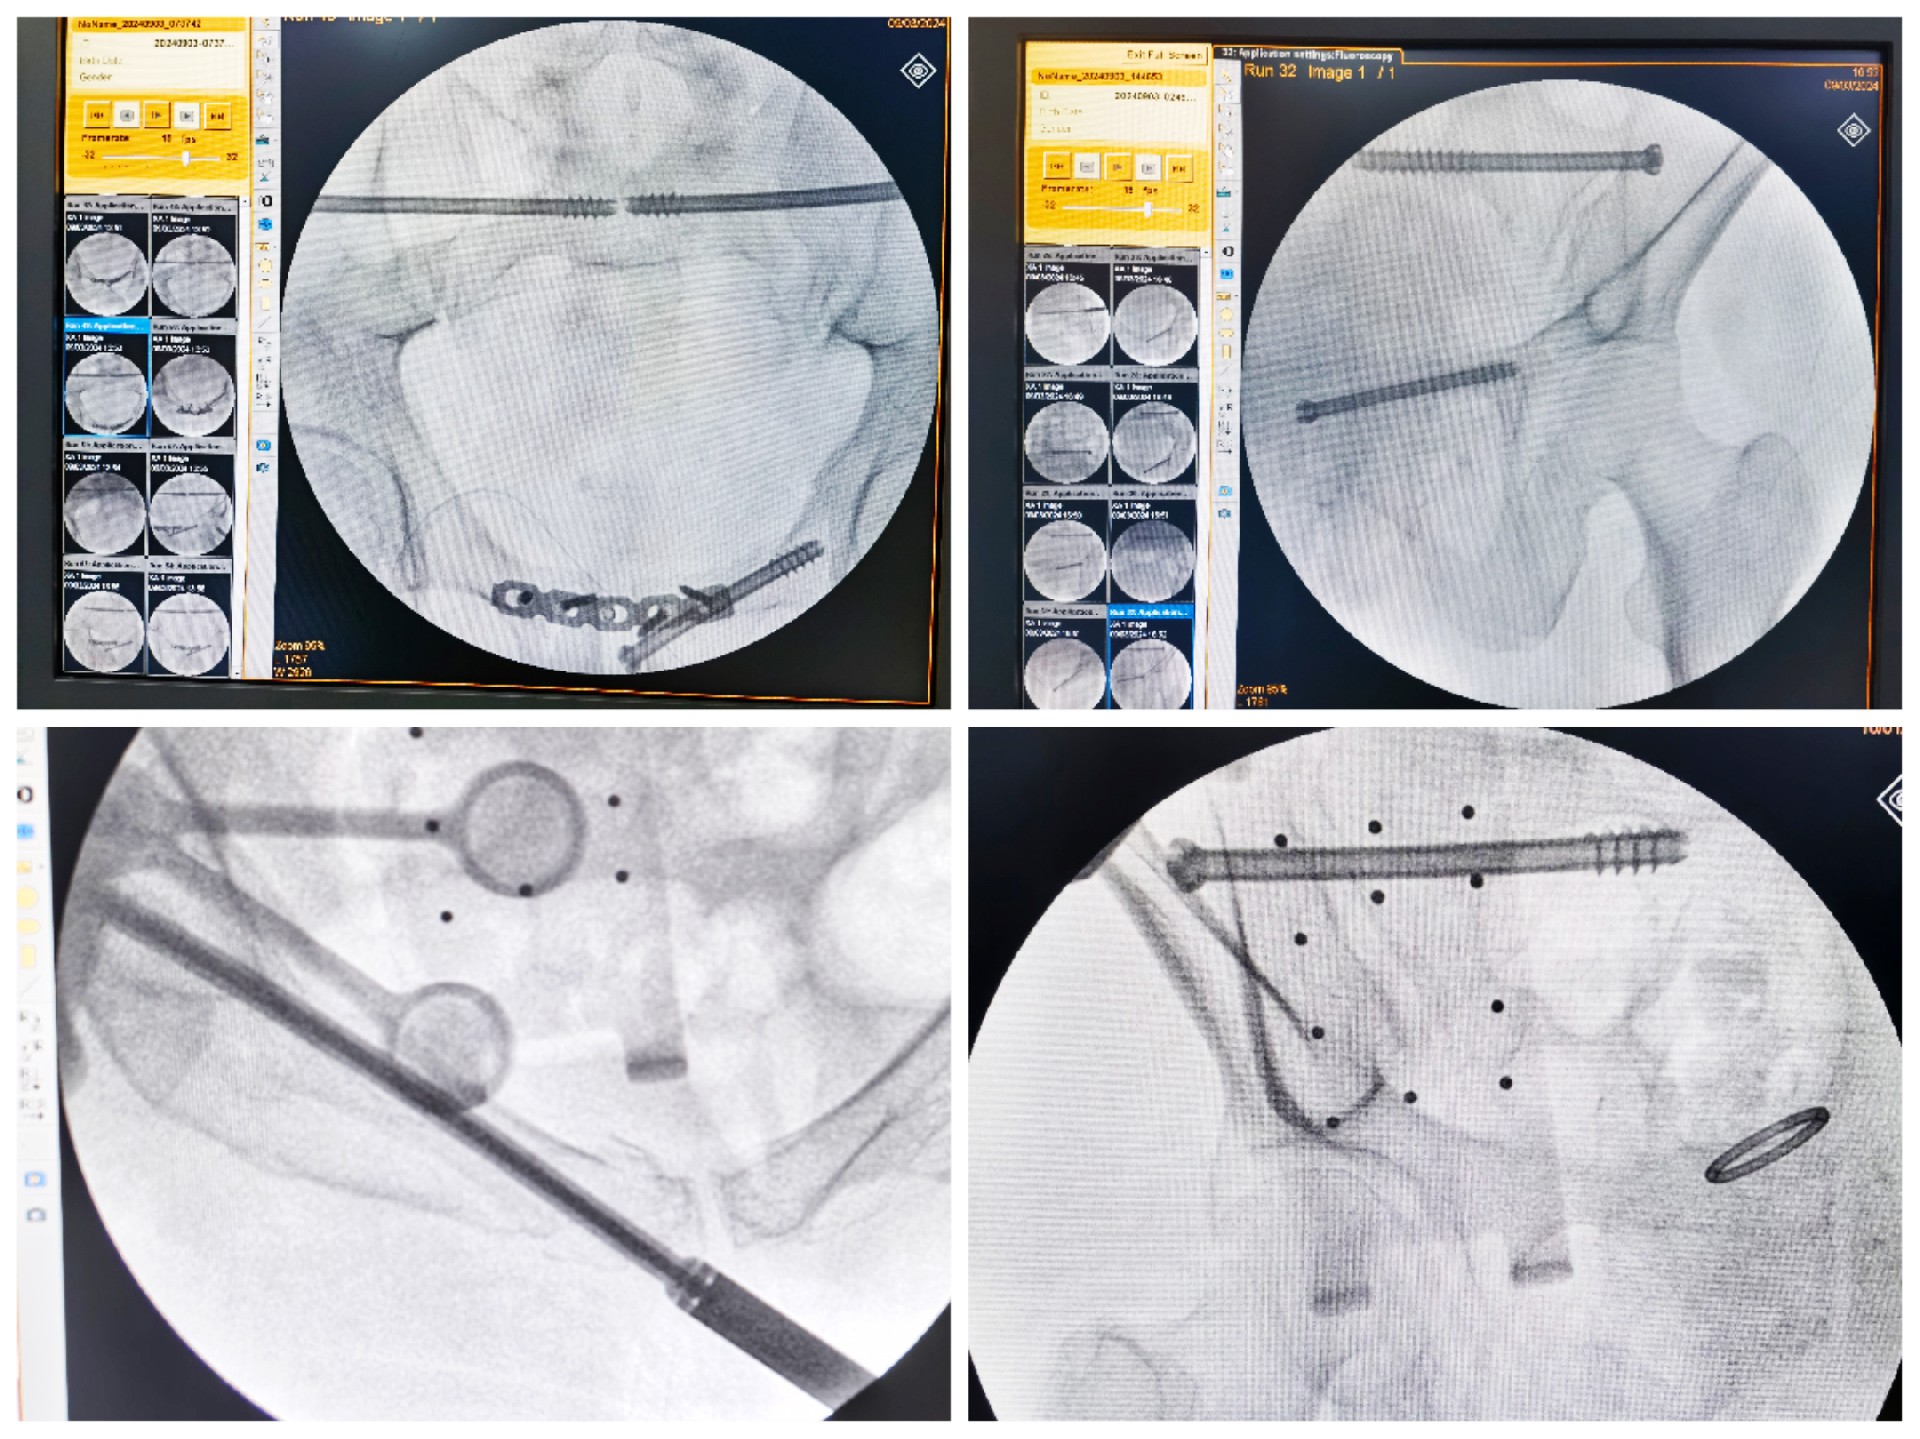

近日,我院骨創外科二病區團隊在宋華科主任的帶領下,在手術室和麻醉科的通力配合下,完成十余例HoloSight知見創傷骨科機器人輔助下骨盆骨折精準微創手術。

傳統的骨盆骨折微創手術中,骶髂螺釘等螺釘置入的難點在于骨盆部位解剖十分復雜,螺釘置入如有偏差極易損傷重要神經及血管,手術不僅依靠手術醫師豐富的經驗,還需要術中反復的C型臂透視及調整,對患者及醫生都有較大輻射。而利用HoloSight知見創傷骨科機器人進行骨盆骨折微創手術,通過高精度光學定位追蹤技術與混合現實技術,使整個微創手術全程可視化,可以在電腦屏幕上實時顯示螺釘的精準置入位置,降低手術風險,提高手術效率及安全性。

術前,手術團隊認真分析討論病例,全面掌握骨盆骨折微創治療的關鍵技術,提前設計手術方案并反復模擬演練手術過程。術中,利用HoloSight知見創傷骨科機器人規劃骨折復位方案及定位螺釘通道,實現精準微創手術。手術通過不足1cm小切口完成,最大程度地減少了術中出血,術中幾乎都是一次性成功精準微創地置入內固定螺釘,減少了醫源性操作對骨折周圍骨質的影響,實現骨折微創固定的同時盡可能提高骨折固定的穩定性,為術后患者的快速康復創造了有利條件。